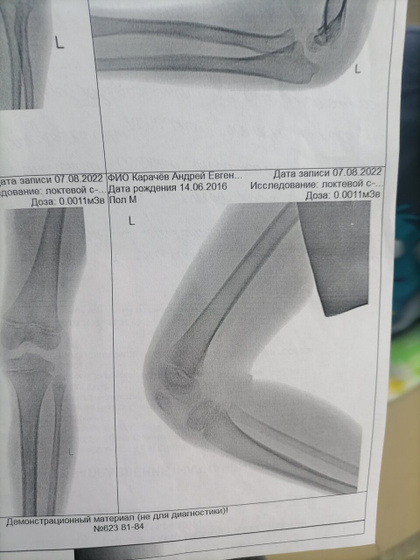

Сходили мы с переломом локтя 12 на прием, все было ок, гипс слегла помятый, сказали сходите на ренген и псм надо ли заменить его, сходили. Сказали все хорошо 29 приходите на снятие, ну мы спокойной и поехали домой, наступает 13,14 число и вот сегодня встаём все с утра и понимаем что гипс сломан в локте прям сгибе прямо, поехали мы с сыном в травму снова, пришли отправили к дежурному травмотологу осмотрел, спросил был ли 12 такой же он гипс? , я тип нет так не ходил, но был изломан внешне деформмрован, сказали не надо менять,отправили по итогу нас сразу поменять гипс, уехали мы домой. Сын встал рано, уснул в 3 часа где то дня, проспал 1.5ч - встал, пошли мы на улицу и он снова нам такой говорит смотрите снова качается гипс тип, мы такие в аху* как так то делают, даже сутки гипс не поддержался… Завтра поедет муж и скажет чтоб забинтовали не вот лангету на заднюю поверхность, а обмотали руку прям, 2 недели ходить ещё, не будем же ежедневно менять ездить его эту лангету.